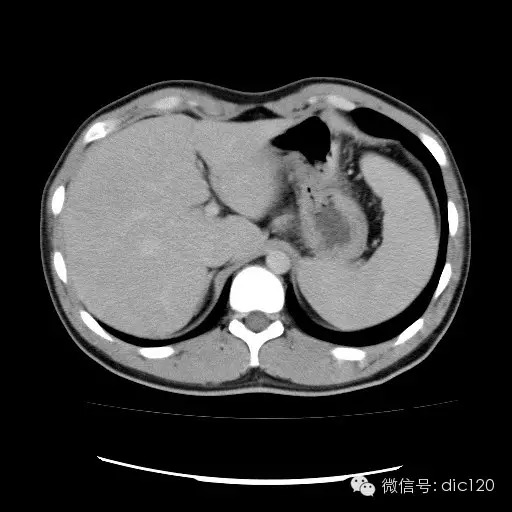

| 影像表现及分析: | 影像表现:动脉期扫描肝右叶紧贴边缘见一过性楔形高密度强化区,边界清,边缘平直,临近血管走形自然,门静脉期期恢复正常肝实质密度,延迟保持与肝实质密度一致。 |

| 疾病总结: | 正常肝脏的双重血供并非2个独立系统,两者之间有许多交通吻合,包括①肝窦间通路.②脉管间途径.③血管丛途径,即胆管周围血管丛途径.当肝脏发生血供障碍时,通过神经一体液因素的调节这些交通吻合支开放,双重供血发生血流量的变化甚至血流方向的改变.肝脏的这种”一过性”灌注异常在SCT表现为肝动脉期一过性肝实质强化(THPE).一过性肝实质强化差异是SCT增强扫描于肝动脉期表现的肝脏一过性灌注异常,大多数情况下它反映了局部肝脏双重血供的重新分布,即局部肝实质门静脉或肝静脉血流量减少,肝动脉血流量增多或为肝动脉门静脉分流或局部肝脏的变异或迷走血供所致。典型CT表现为肝动脉期一过性楔形或三角形高密度强化区,边缘平直,常位于肝脏边缘部位,其中血管走行正常,门静脉期恢复为正常肝实质密度。放射学医师应加强对一过性肝实质强化CT表现的认识。 |